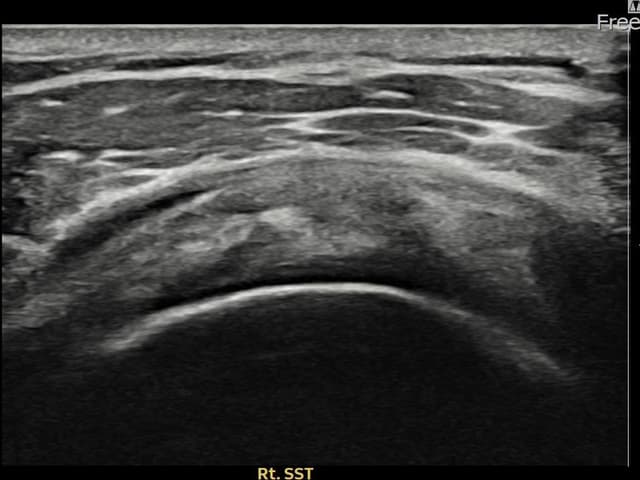

[촬영시기:23.11.28~24.02.06]

[어깨인대 축소봉합술] 우측 어깨 후방 통증과 팔을 바깥으로 돌릴 때 통증이 심해 내원하셨습니다.